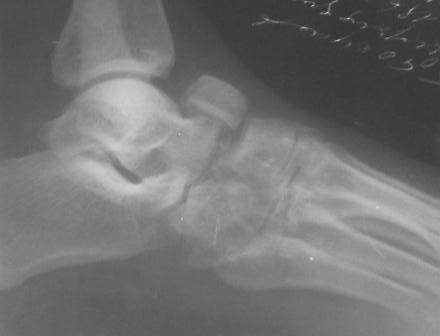

Обратился больной 46 лет. 3 месяца назад получил травму левой стопы в результате ДТП, живет в отдаленный степной зоне, лечился у местного табиба. Ходит при помощи двух костылей, наступая на пятку, на передный отд стопы наступать не может из-за боли, умеренная отечность стопы и деформация в обл. ладьевидной кости, движения в голеностопном суставе в польном обьеме, в средном отд ограничены и болезненны. Уважаемые коллеги, я пока не знаю что делать, помогите, пожалуйста, советами! С уважением Абдурашид.

По данному случаю, оказалось 3 месяца назад было произведена Р-графия в райбольнице, но больной предпочел лечится у табиба. Присылаю первичные снимки.

Да, наш с Вами диагноз, Абдурашид, подтвердился. Я бы предпочёл артродез, фиксация- в самом простом варианте-винтами 3,5 или 4,5 . Отломок послужит аутотрансплантатом. Плюс внешняя иммобилизация. С уважением, Волна